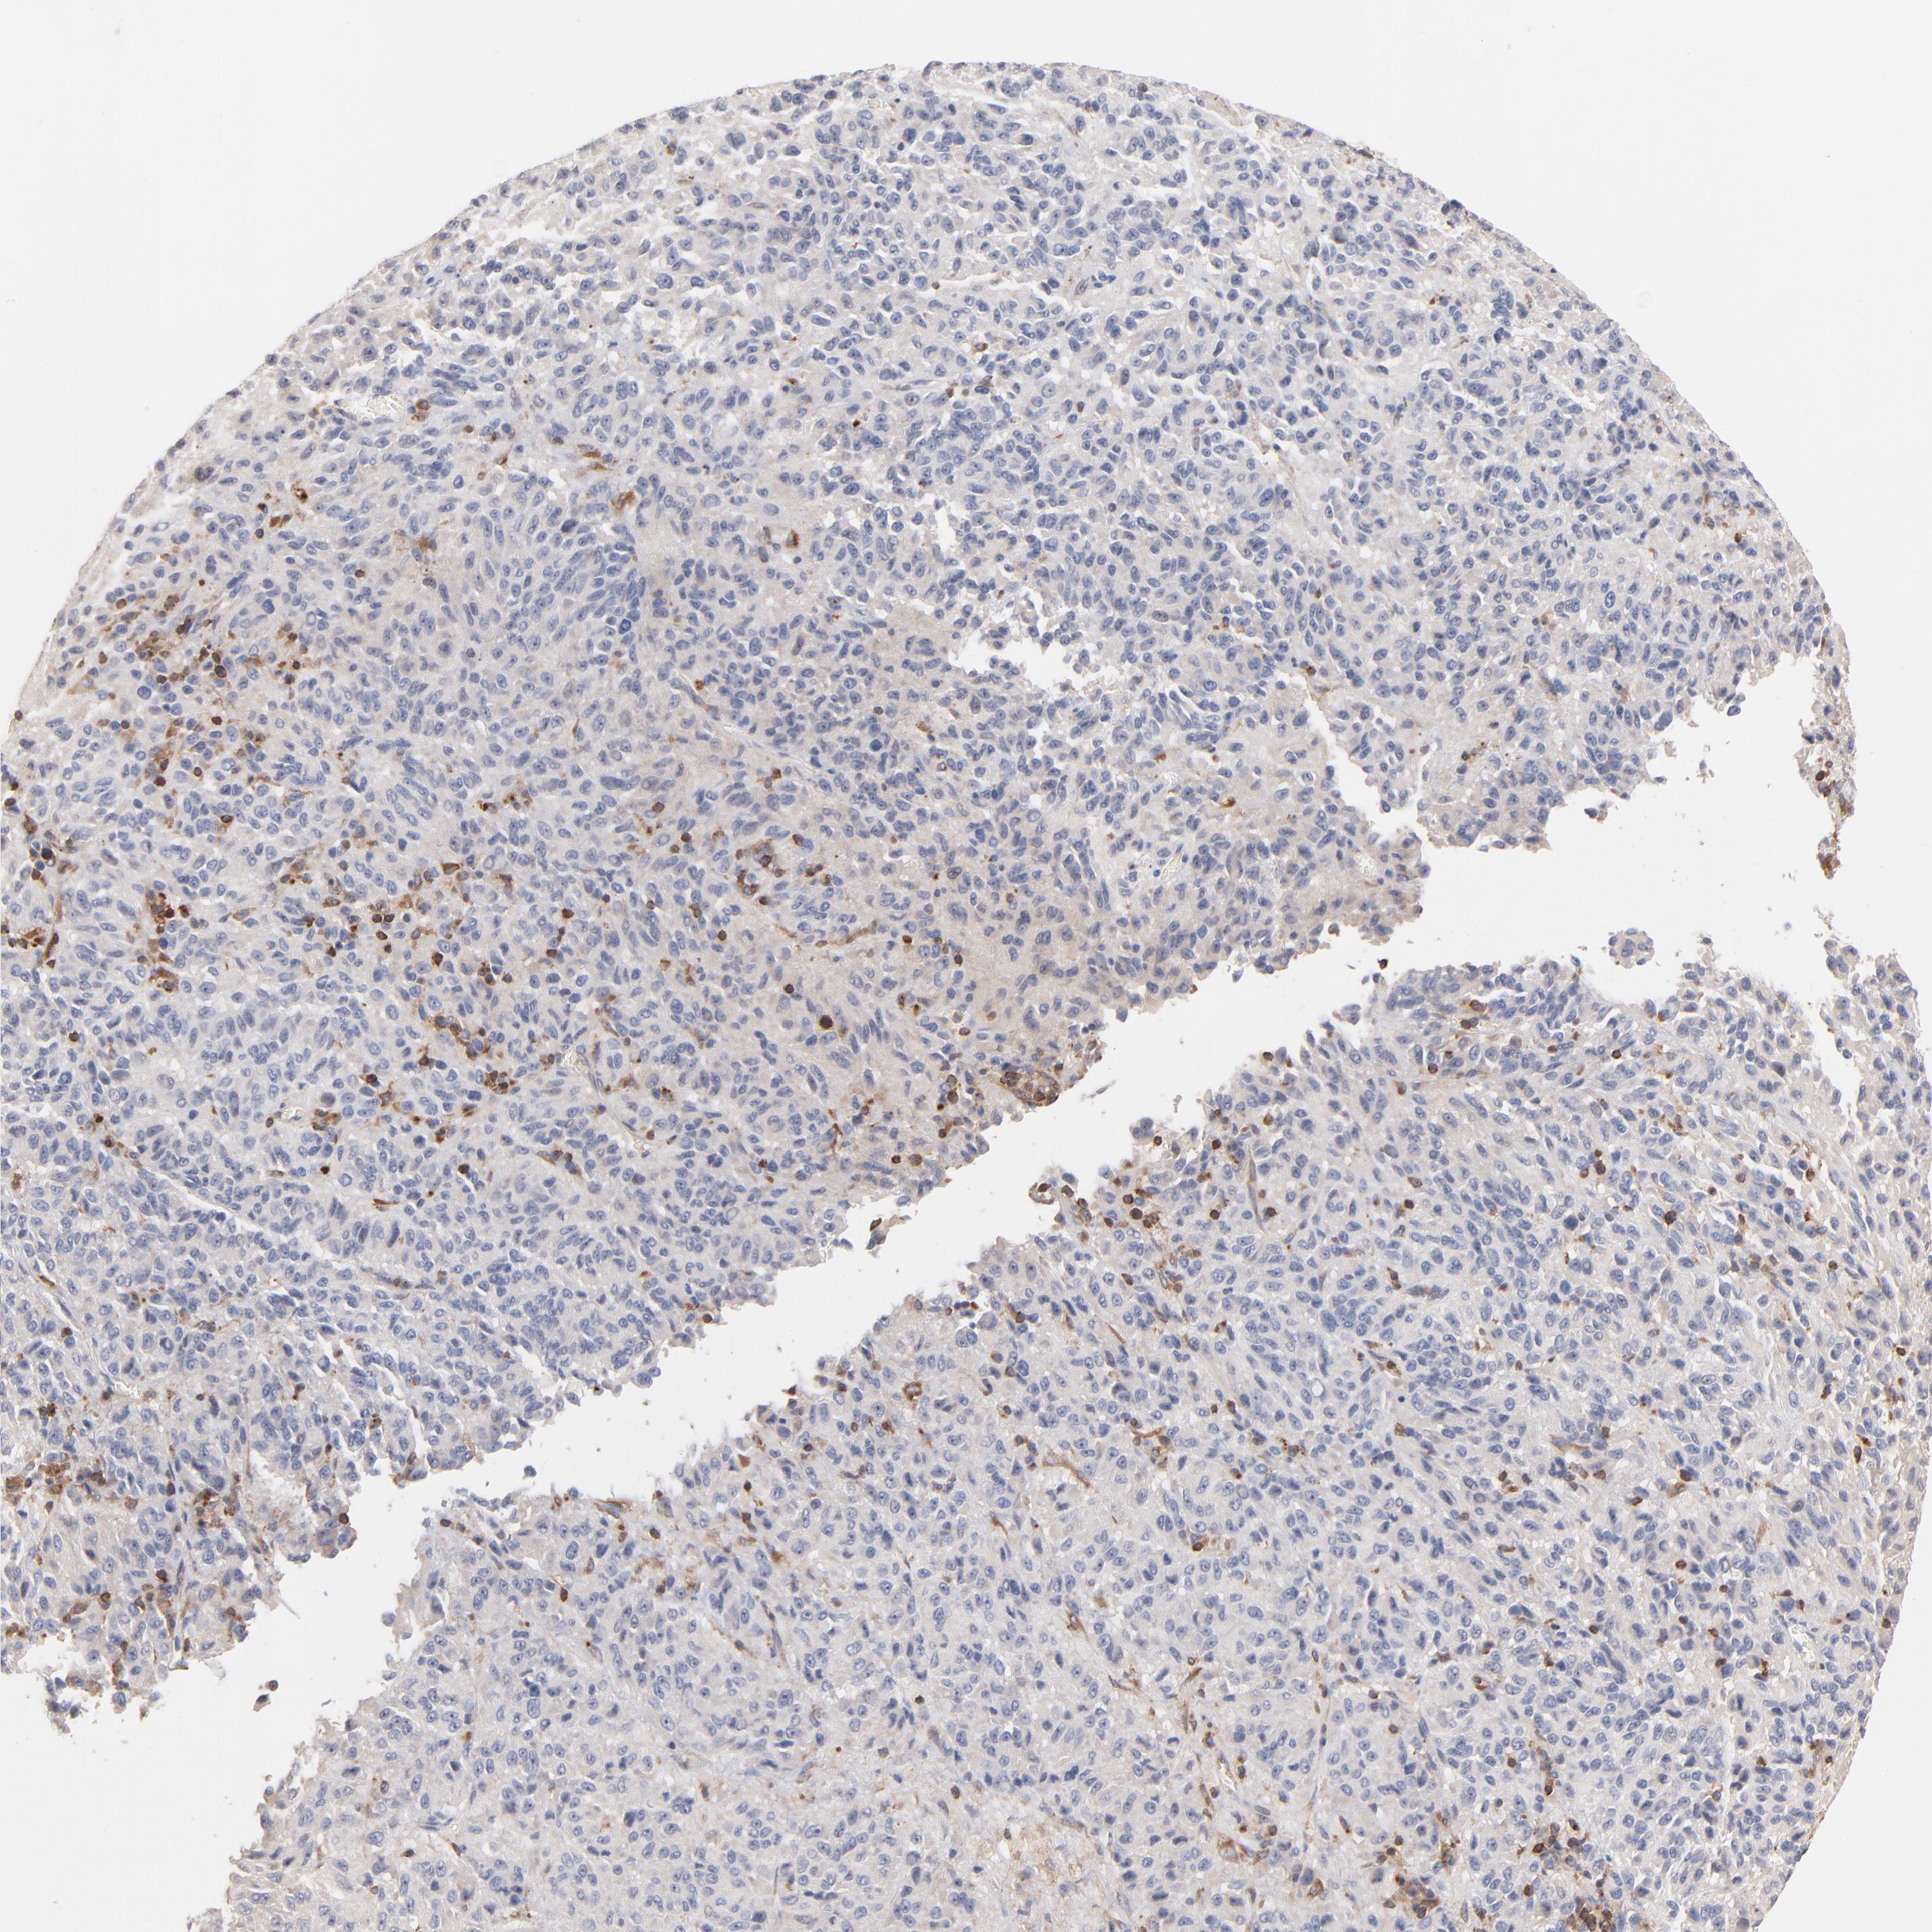

MELANOMA - Protein expressioni

A mouse-over function shows sample information and annotation data. Click on an image to view it in a full screen mode. Samples can be filtered based on level of antibody staining by selecting one or several of the following categories: high, medium, low and not detected. The assay and annotation is described here.

Note that samples used for immunohistochemistry by the Human Protein Atlas do not correspond to samples in the TCGA dataset.

Antibody stainingi

Antibody staining in the annotated cell types in the current human tissue is reported as not detected, low, medium, or high, based on conventional immunohistochemistry profiling in selected tissues. This score is based on the combination of the staining intensity and fraction of stained cells.

Each image is clickable and will lead to virtual microscopy that enables deeper exploration of all samples and also displays staining intensity scores, fraction scores and subcellular localization as well as patient and tissue information for each sample.

Antibody HPA003739

Antibody CAB009737

Staining

High

Medium

Low

Not detected

Intensity

Strong

Moderate

Weak

Negative

Quantity

>75%

75%-25%

<25%

None

Location

Nuclear

Cytoplasmic/membranous

Cytoplasmic/membranous,nuclear

Malignant melanoma, NOS

Malignant melanoma, Metastatic site